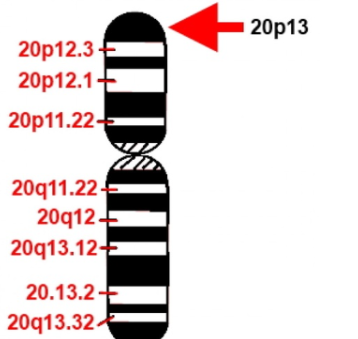

В ходе исследований было установлено, что возбудитель прионных заболеваний – мутированная (инфекционная) форма низкомолекулярного белка, названного прионным протеином (PrP). Прион (от англ. Proteinaceous infection particle) – белковоподобная инфекционная частица. Нормальная спиралевидная форма прионного протеина PrPС обнаружена в организме всех млекопитающих, в том числе и человека. Её кодирует единственный ген под названием PRNP, высокие уровни устойчивой экспрессии которого обнаруживают в нейронах в пятьдесят раз чаще, чем в глии.

Ген PRNP, кодирующий PrP, обладает высокой степенью консервативности. Несмотря на это, в настоящее время установлены около сорока различных мутаций этого гена, которые связаны с различными прионными болезнями. В ряде случаев превращение нормального белка в прионный связано с мутациями этого гена. К таким заболеваниям относятся спорадичекая форма болезни Кройтцфельдта-Якоба, синдром Герстманна-Штреусслера-Шейнкера и фатальная семейная бессонница. Особую роль в этом имеют полиморфизм кодона 129, кодирующий метионин либо валин.